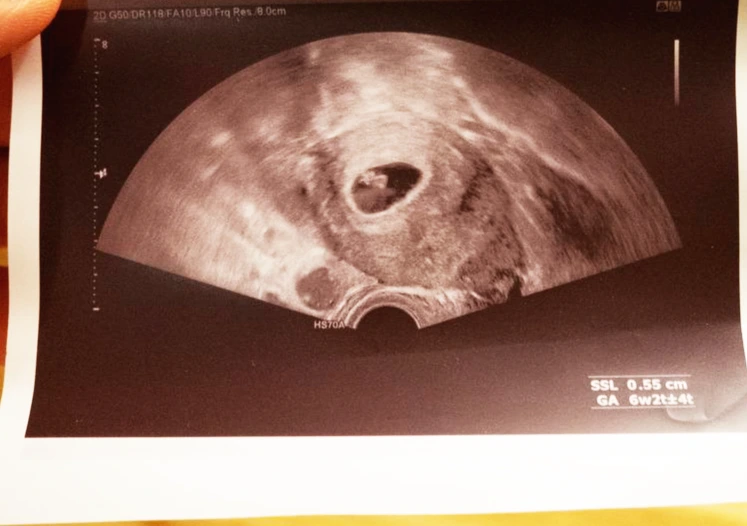

그렇게 산부인과에 다니기 시작하며 출산까지 10달의 길고 긴 여정이 시작됐다. 먼저 산부인과에서 “임신입니다! 축하합니다!”하는 확실한 대답을 듣고 싶었다. 주변에 조언을 구해 찾아간 우리의 담당의는 아직 아이의 핵이 안 보인다며 일주일만 기다려보자고 했다. 이게 늦게 수정되어서 일 수 있고 아님 임신이 아닐 수도 있기 때문이다. 후우, 입이 여러모로 간지러웠다. 그러나 아내를 위해 최대한 침착했다. 자칫 내가 심리적으로 동요하다간 그녀의 감정도 왠지 그네를 탈 것 같았다. 그렇게 덥고 더우며 지루한 일주일이 지나 우린 드디어 담당의에게 확진을 들었다. 살짝 구식으로 보이는 장비로 초음파 사진을 보여주며, 정말 그가 설명해주지 않으면 뭐가 뭔지 모르겠는 사진으로 우리 아이가 엄마와 함께 있음을 설명해줬다. 그러며 줄줄이 앞으로 해야 할 일에 대한 설명도 덧붙였다. 그리고 그 날, 부모님들께 전화를 드렸다. 안정기에 접어드는 3달을 기다릴 수도 있었으나 아내의 입덧이 생각보다 일찍 심해져 얼른 음식이든 뭐든 부모님의 도움을 받아야 했다.

날짜 상으론 임신 2개월째 초음파다운 초음파 검사를 했다. 사실 담당의가 돋보기안경을 위로 추켜세우며 자세히 설명해주지 않으면 뭐가 뭔지 모른다.